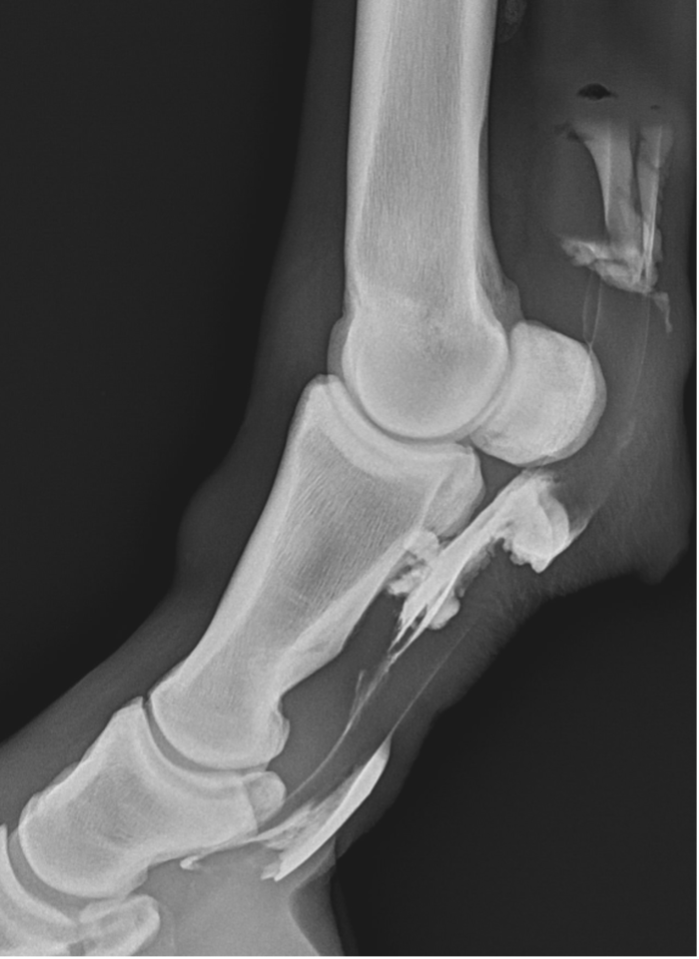

Recently, the gelding developed acute tenosynovitis of the left hind digital flexor tendon sheath (DFTS) following a competition. Despite the owner’s efforts, which included icing, wrapping, and confinement for seven days, there was no improvement in the effusion of the DFTS.

Upon further examination, contrast radiographs and ultrasound scans failed to identify any significant abnormalities apart from swollen synovium within the DFTS. To address this issue, our veterinary team administered 5mg of triamcinolone acetonide along with 20mg of HA, complemented by a compression wrap. Subsequently, the horse underwent a two-week confinement period in a small yard, followed by gradual reintroduction to exercise through 10 minutes of hand walking twice daily, with the distal limb wrapped for additional support.